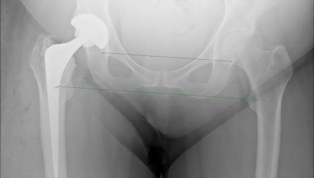

The x-rays below show what cemented, un-cemented and hybrid hip replacements look like.You can also see how the surgeon can measure the patients leg length post operatively on the hybrid x-ray.

HYBRID:

In older more active patients another option is to use an

un-cemented socket(Pinnacle) with a cemented femoral

stem(Exeter). The survivorship of cemented stems is

significantly better than cemented sockets. Also, using

an un-cemented socket allows the surgeon the option of

changing the bearing surface of the hip replacement.